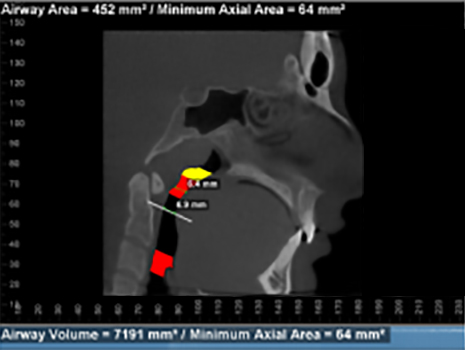

The patient below experiences the following symptoms:

- Struggling to breathe during sleep

- Snoring

- Waking unrefreshed

- Daytime fatigue

- Easily distracted

- Neck pain

- Buzzing in both ears once or twice a week for about a one minute duration.

Before and after images of patient after 9 months of successful treatment: